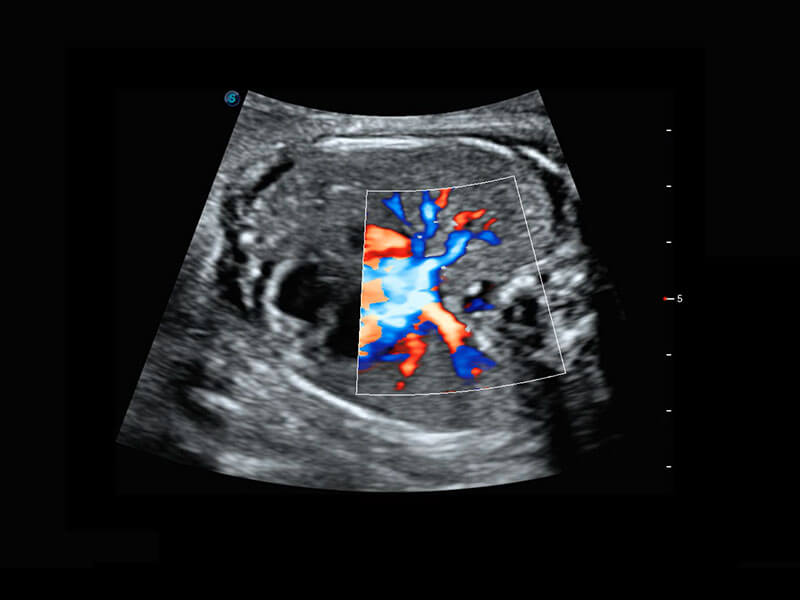

胎儿体循环

P60搭载一系列胎儿心脏成像技术,实现精细的胎儿心脏评估。

四腔心血流